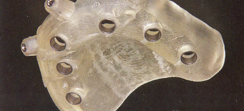

最低4本のインプラントを埋入し、それらを連結し、半日で固定式の仮歯まで入れて審美性、機能性を一日でとりもどせる革新的な治療。